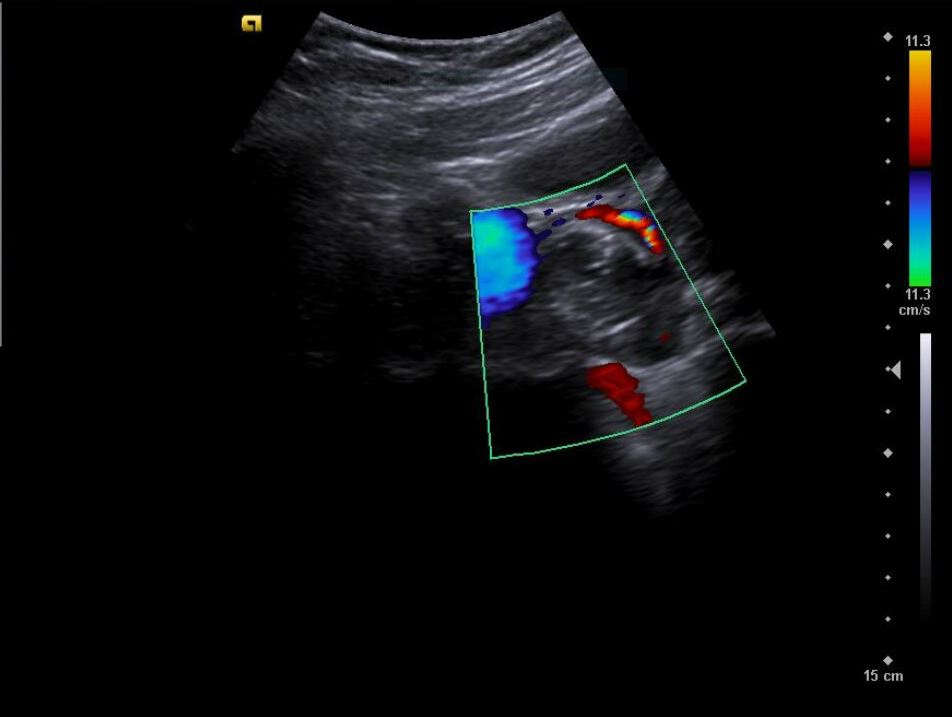

• Riñones sin hidronefrosis; jets ureterales presentes. No centelleo pielocalicial.

• Revisión ginecológica incidental muestra una imagen heterogénea en anexos: masa de aspecto solidoquístico en ovario derecho (43 × 33 mm), con zona hiperecoica y posible componente quístico. Se plantea teratoma como primera hipótesis diagnóstica.